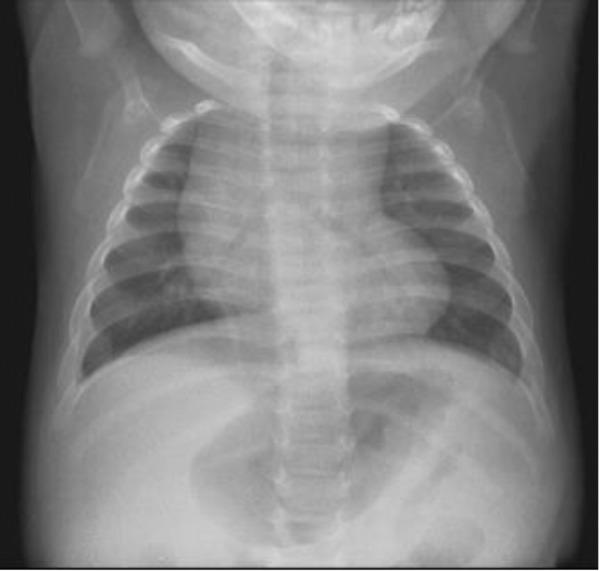

Troyer syndrome (MIM#275900) is an autosomal recessive form of complicated hereditary spastic paraplegia. It is characterized by progressive lower extremity spasticity and weakness, dysarthria, distal amyotrophy, developmental delay, short stature, and subtle skeletal abnormalities. It is caused by deleterious mutations in the gene, encoding spartin, on Chromosome 13q13. Until now, six unrelated families with a genetically confirmed diagnosis have been reported. Here we report the clinical findings in three brothers of a consanguineous Moroccan family, aged 24, 17, and 7 yr old, with spastic paraplegia, short stature, motor and cognitive delay, and severe intellectual disability. Targeted exon capture and sequencing showed a homozygous nonsense mutation in the gene, c.1369C>T (p.Arg457*), in the three affected boys.

特罗耶综合征(MIM#275900)是一种常染色体隐性遗传的复杂遗传性痉挛性截瘫。其特征为进行性下肢痉挛和无力、构音障碍、远端肌萎缩、发育迟缓、身材矮小以及细微的骨骼异常。它是由位于13号染色体q13区域的编码斯巴丁的基因突变所致。到目前为止,已报道了6个经基因确诊的不相关家庭。在此,我们报告一个近亲结婚的摩洛哥家庭中3名兄弟的临床症状,他们的年龄分别为24岁、17岁和7岁,患有痉挛性截瘫、身材矮小、运动和认知发育迟缓以及严重智力残疾。靶向外显子捕获和测序显示,这3名患病男孩的该基因存在纯合无义突变,即c.1369C>T(p.Arg457*)。